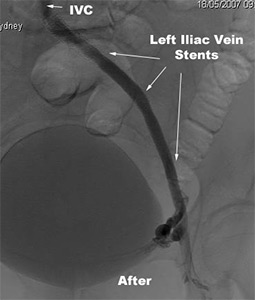

The following case highlights the use of percutaneous revascularisation in the setting of extensive lower limb venous thrombosis.

A 45 year old female developed an extensive left leg deep vein thrombosis 7 days following lumbar spine surgery. Acute thrombolysis was contraindicated. Anticoagulation was commenced and after 6 months therapy, there was recanalisation of the left femoral and popliteal DVT but the left iliac vein remained occluded.The patient had venous claudsication and a persistently swollen and painful left leg. An IVC filter was inserted through the right leg vein. Angiographic images were obtained of the inferior vena cava (IVC) and left leg veins showing occlusion of the left iliac vein with extensive collateral vein formation (before image below). The patient then had angioplasty and stenting of the left iliac vein with restoration of venous return to the left leg (after image below).